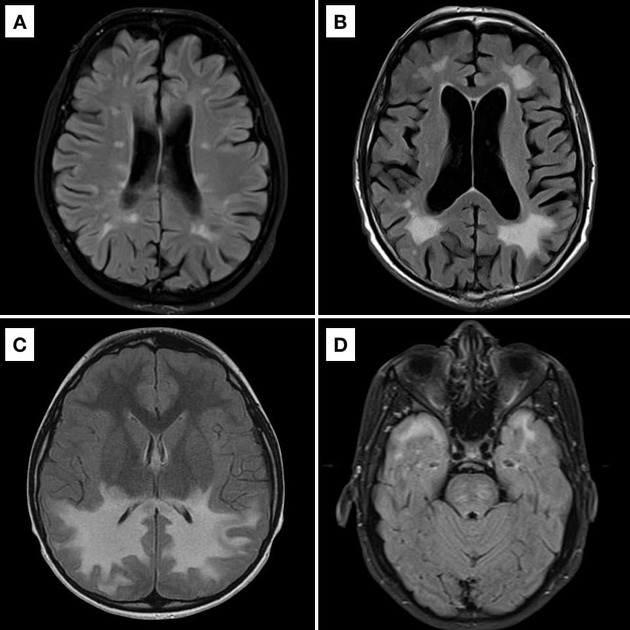

Brain stem ischemia is due to blockage of blood vessels. Microvascular ischemic disease is often detected on an mri of the brain. In this mri of the brain there are multiple white spots that appear very brightly in the brain tissue.

Balance issues and frequent falls. This appears as small white dots on. Chronic small vessel disease or chronic microvascular ischemic changes is a very common finding on head ct as we age.

Chronic Microvascular Ischemic Changes In The Brain Are Often Picked Up Incidentally On A Scan Of The Brain, Most Typically An Mri.

Untreated, it can lead to dementia, stroke and difficulty walking. Mri of the brain with ischemic changes. Modifications to these blood arteries can result.

Some radiologists refer to this as age related white. Cerebral small vessel disease (alternatively subcortical small vessel disease, chronic small vessel disease , or cerebral microangiopathy ) is an umbrella term for lesions in. Dizziness/vertigo and imbalance are the most common symptoms of vertebrobasilar ischemia.